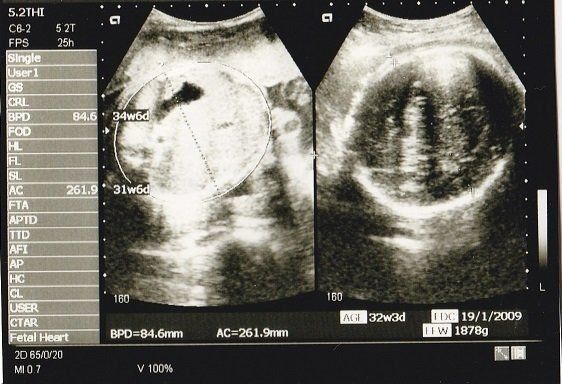

ちゃじゅびさんの妊娠32週目のエコー写真 おなかもぱんぱんです。

不妊治療や2度の流産経験を経て「初めての出産」。日々成長する胎児の記録をエコー画像で振り返る

AC(おなかの周囲の長さ)などから、赤ちゃんの推定体重を計算するようです。赤ちゃんのおなかも大きくなっていますが、お母さんのおなかもぱんぱんです。